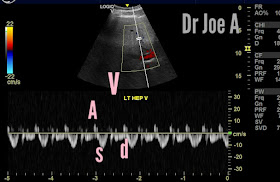

Here's what I observed on Doppler trace of the right and left hepatic veins.

There are broadly 4 waves in a hepatic vein on spectral Doppler tracing. A, S, V and D waves.

A wave: The A wave is the first negative wave in the hepatic vein spectral Doppler waveform. It represents the brief period of increased resistance to blood flow caused by atrial contraction. The A wave is usually smaller and less prominent than the S and D waves.

S wave: The S wave is the first positive wave in the hepatic vein spectral Doppler waveform. It is caused by the initial surge of blood flow into the hepatic vein during the systolic phase of ventricular contraction. The S wave is usually sharp and well-defined.

V wave: The V wave is the second negative wave in the hepatic vein spectral Doppler waveform. It represents the early diastolic phase, during which the ventricles relax and blood flow decreases. The V wave is usually lower in amplitude and longer in duration than the A wave.

D wave: The D wave is the second positive wave in the hepatic vein spectral Doppler waveform. It represents the passive filling of the hepatic vein during the late diastolic phase, when the atria contract and push blood into the ventricles. The D wave is usually broader and less steep than the S wave.

In a normal hepatic vein spectral Doppler waveform, these four waves form a triphasic pattern with three peaks (S, D, and V) and two troughs (A and V), reflecting the phases of the cardiac cycle and blood flow dynamics in the liver. However, the waveform can be affected by various factors such as age, sex, body position, and cardiac function. Therefore, it is important to interpret the waveform in the context of the patient's clinical history and other imaging findings.